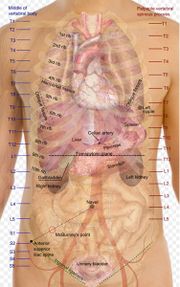

| 22. 11. 2011, 11:14 | Projekce organu trupu.jpg (soubor) |  | 45 kB | Webmaster | 2 | |